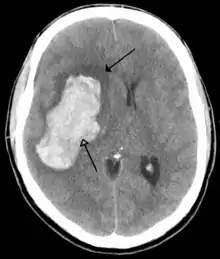

The brain is protected by the skull, suspended in cerebrospinal fluid, and isolated from the bloodstream by the blood–brain barrier. However, the brain is still susceptible to damage, disease, and infection. Damage can be caused by trauma, or a loss of blood supply known as a stroke. The brain is susceptible to degenerative disorders, such as Parkinson's disease, dementias including Alzheimer's disease, and multiple sclerosis. Psychiatric conditions, including schizophrenia and clinical depression, are thought to be associated with brain dysfunctions. The brain can also be the site of tumours, both benign and malignant; these mostly originate from other sites in the body.

Brain tumours can be either benign or cancerous. Most malignant tumours arise from another part of the body, most commonly from the lung, breast and skin.[173] Cancers of brain tissue can also occur, and originate from any tissue in and around the brain. Meningioma, cancer of the meninges around the brain, is more common than cancers of brain tissue.[173] Cancers within the brain may cause symptoms related to their size or position, with symptoms including headache and nausea, or the gradual development of focal symptoms such as gradual difficulty seeing, swallowing, talking, or as a change of mood.[173] Cancers are in general investigated through the use of CT scans and MRI scans. A variety of other tests including blood tests and lumbar puncture may be used to investigate for the cause of the cancer and evaluate the type and stage of the cancer.[173] The corticosteroid dexamethasone is often given to decrease the swelling of brain tissue around a tumour. Surgery may be considered, however given the complex nature of many tumours or based on tumour stage or type, radiotherapy or chemotherapy may be considered more suitable.[173]

Most strokes result from loss of blood supply, typically because of an embolus, rupture of a fatty plaque causing thrombus, or narrowing of small arteries. Strokes can also result from bleeding within the brain.[187] Transient ischaemic attacks (TIAs) are strokes in which symptoms resolve within 24 hours.[187] Investigation into the stroke will involve a medical examination (including a neurological examination) and the taking of a medical history, focusing on the duration of the symptoms and risk factors (including high blood pressure, atrial fibrillation, and smoking).[188] Further investigation is needed in younger patients.[189] An ECG and biotelemetry may be conducted to identify atrial fibrillation; an ultrasound can investigate narrowing of the carotid arteries; an echocardiogram can be used to look for clots within the heart, diseases of the heart valves or the presence of a patent foramen ovale.[189] Blood tests are routinely done as part of the workup including diabetes tests and a lipid profile.[189]

Some treatments for stroke are time-critical. These include clot dissolution or surgical removal of a clot for ischaemic strokes, and decompression for haemorrhagic strokes.[190][191] As stroke is time critical,[192] hospitals and even pre-hospital care of stroke involves expedited investigations – usually a CT scan to investigate for a haemorrhagic stroke and a CT or MR angiogram to evaluate arteries that supply the brain.[189] MRI scans, not as widely available, may be able to demonstrate the affected area of the brain more accurately, particularly with ischaemic stroke.[189]